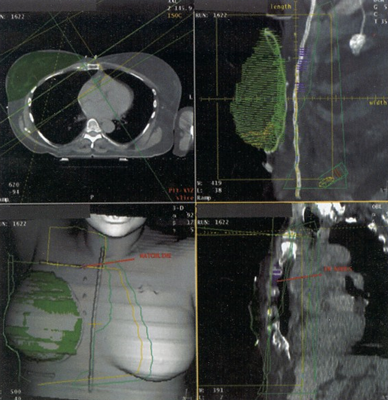

Case History: 24-year-old male with enlarged cervical lymph nodes associated with weight loss and fever.